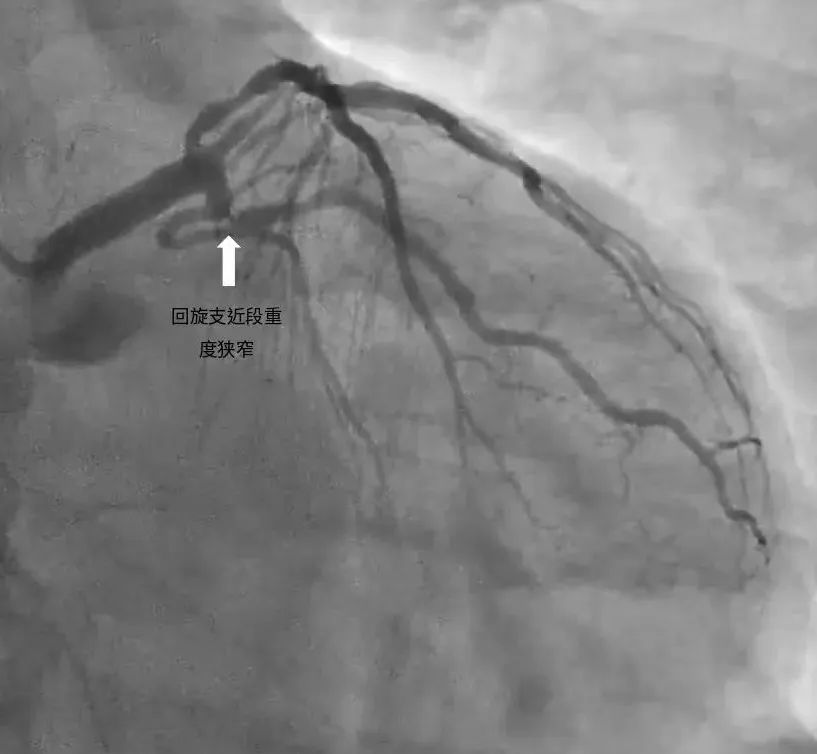

左回旋支近端次全闭塞

左回旋支近段使用药物球囊后,狭窄基本消失